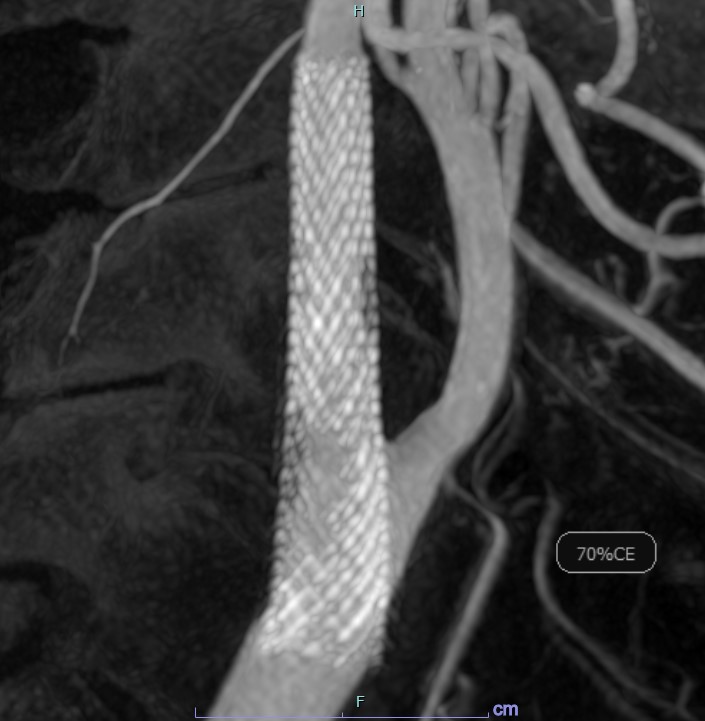

脳血管撮影

脳血管撮影では、頭頸部の血管をカテーテルから造影剤を流して撮影します。血管の走行を観察したり、必要に応じて血管の狭窄や閉塞を広げる治療や、動脈瘤をコイルで塞栓する治療、脳腫瘍などへの栄養血管に対して手術前の塞栓術を行ったりします。脳の血管をみる検査にはCTやMRIなどといった撮影もありますが、血管撮影装置での脳血管撮影ではそれらよりも細かい血管の状態まで観察することができます。

内頚動脈狭窄症へのステント術